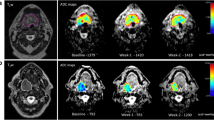

Combined modality response

To determine the utility of combining multiple imaging modalities, the most accurate FDG-PET/CT parameter and DWI parameter that correlated to local recurrence (highest ROC value in AUC analysis) were chosen for subsequent analysis. Optimum cut-off values from the two parameters were used to determine patient’s response in each imaging modality. Patients were subsequently divided into three groups based on those that had favourable response in both FDG-PET/CT and DWI imaging; mixed response (good PET and poor DWI, or poor PET and good DWI); or poor response in both imaging modalities (for a representative example of three groups, see Fig. 4). The three groups were compared to local recurrence status using the Pearson chi-squared test, using Cramer’s V test to check the strength of association to determine the utility of combining multiple parameters in improving predictive ability.

To test the primary hypothesis of the added value of combining DWI and FDG-PET/CT parameters, ∆ADCmean and ∆MTV at week 3 were chosen to define response in DWI and FDG-PET/CT imaging. Using optimal cut-off value of ∆Week 3 ADCmean (> 24.4%) and ∆MTV (< 50.4%) to define response in each imaging modality, 20 patients were defined as favourable responders (> 24.4% ∆Week 3 ADCmean, and > 50.4% ∆MTV), 9 patients were defined as unfavourable responders (< 24.4% ∆Week 3 ADCmean, and <50.4% ∆MTV), and 12 patients were defined as mixed responders. In favourable responders, no patients (0/20) had local recurrence. In mixed responders, 17% (2/12) had local recurrence. In unfavourable responders, 78% (7/9) had local recurrence (for a representative example of three groups, see Fig. 4). The Kaplan-Meier analysis of local recurrence stratified by the above three response groups (subgroups) is shown in Fig. 5. Using a combination of ∆ADCmean and ∆MTV improved the strength of correlation to local recurrence (Cramer’s V 0.736, p ≤ 0.001, Pearson chi-squared test) compared to using individual parameter alone (Cramer’s V 0.693, 0.586).